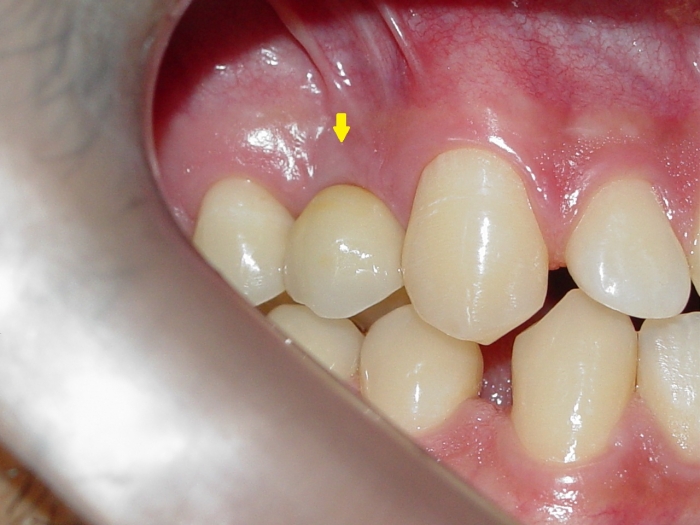

Imagens do caso terminado, em novembro de 2011